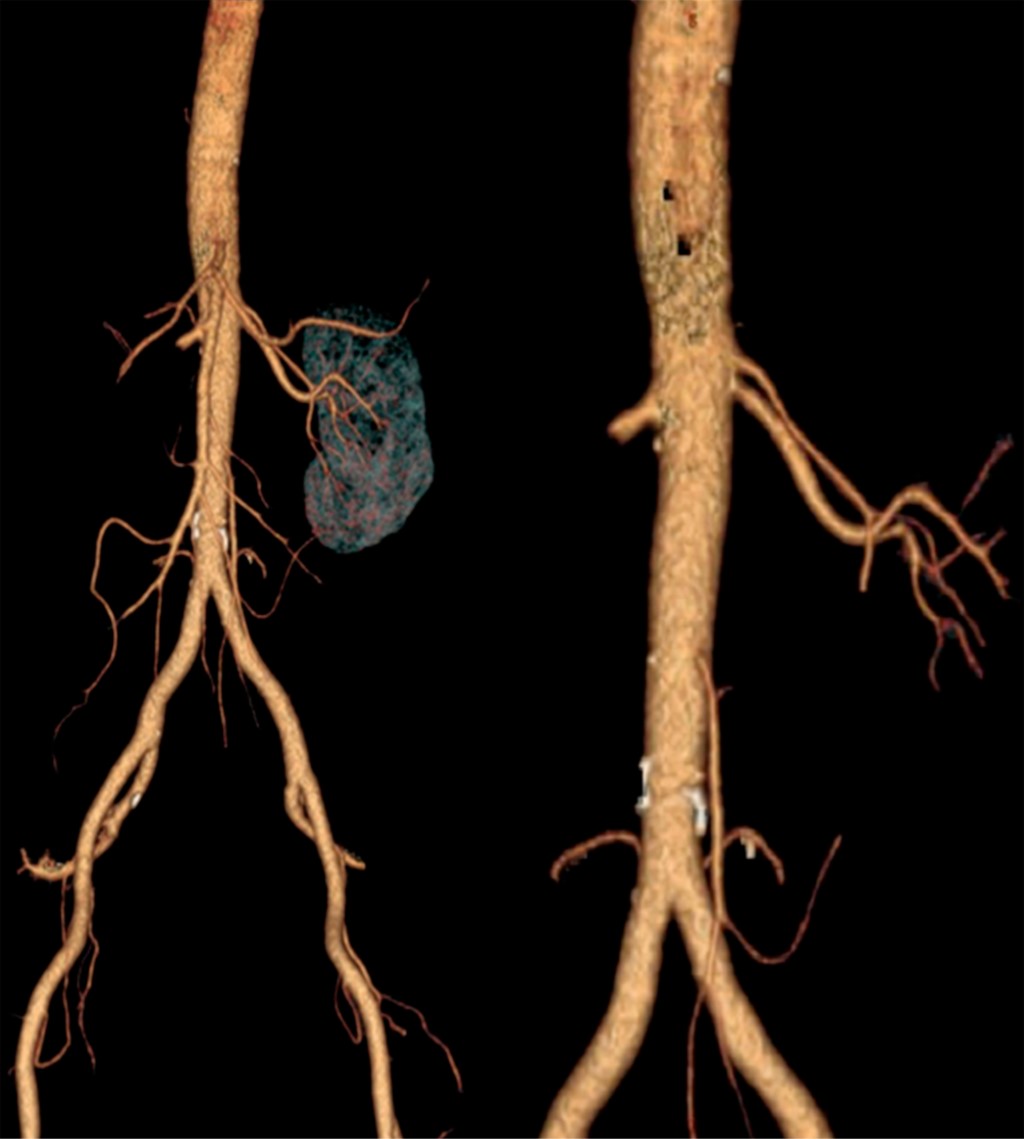

En fase arterial, la angiotomografía evidencia amputación de arteria renal derecha desde su origen con la consecuente ausencia de fase nefrográfica (Figuras 1 y 2).

A nivel del hilio se encontraron cuatro arterias renales, resultado de la bifurcación de una arteria renal principal como variante anatómica (Figura 3).